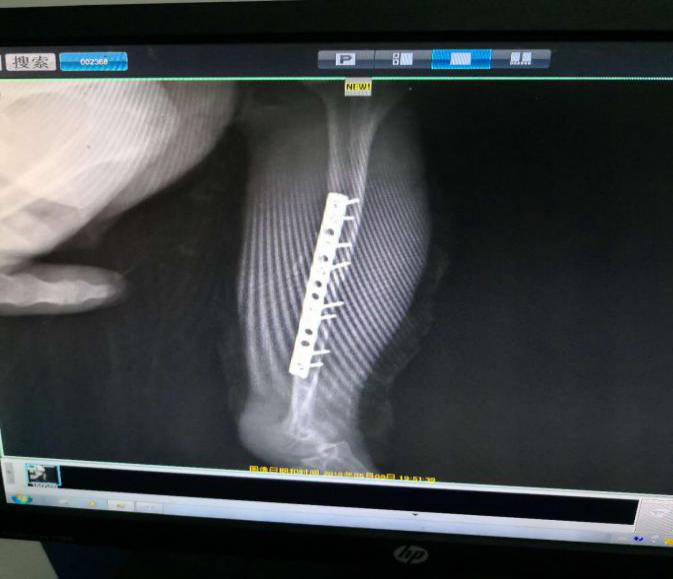

X光显示我骨折了

在李主任的猛禽救护中心,我见到了很多和我一样在这里养伤的小伙伴们,他们有的被弹弓打伤,有的被从小掏窝...不过小伙伴都被照顾的很好,我很开心能够来到这个温暖的家。李主任特地给我准备了一间宽敞的房间,每天不辞辛苦地给我涂药检查伤口,鸽子老鼠牛肉轮番给我补身体,在这里我度过了鸮生最无忧无虑的时光。

为了不耽误我的病情,身为警察叔叔的李主任在下班后马不停蹄的将我送到中心的合作救助单位—润珑宠物医院。经过半小时的手术后,我的断骨处被成功地接了回去,接下来,我需长时间的静养,直到断骨长好。